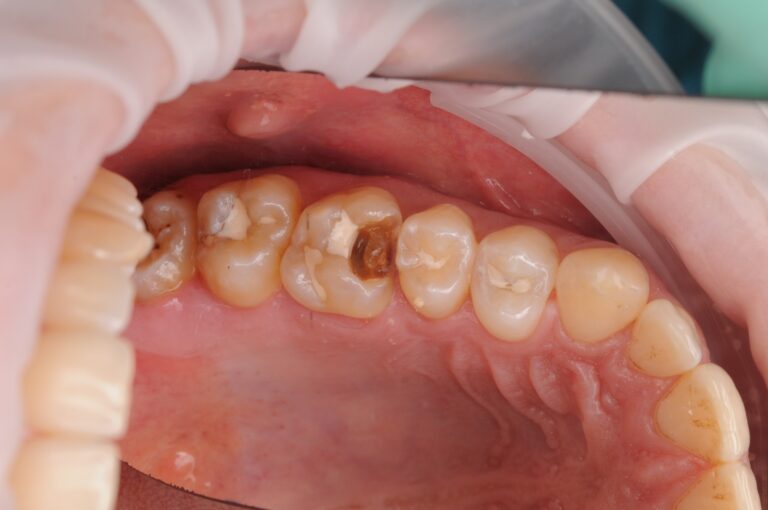

Второе фото: снимаем пломбу — и видим реальность

Под пломбой — глубокий, обширный кариес,

который не был заметен снаружи.

Это важный момент:

Если пломба не вызывает боли — это не значит, что всё в порядке.

Кариес под пломбой может развиваться тихо, долго —

пока не станет поздно.